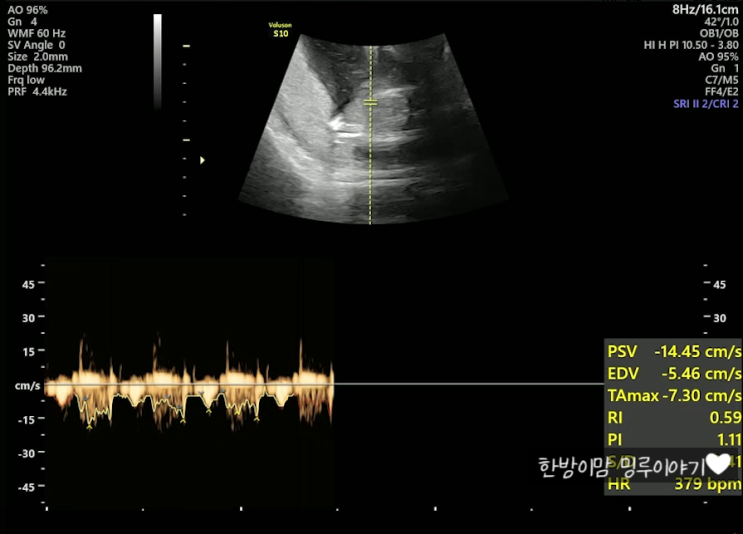

임신중일기_6. 30주차 초음파. 얼굴 보기 힘든 한방이, 손은 야무지게 생겼구나??(한나산부인과 백일해주사, 바우처결제)

이번엔 한나산부인과, 30주 정기검진 이야기!! 예약하고 방문하니, 남편 백일해주사맞는 것까지 30분정도밖...